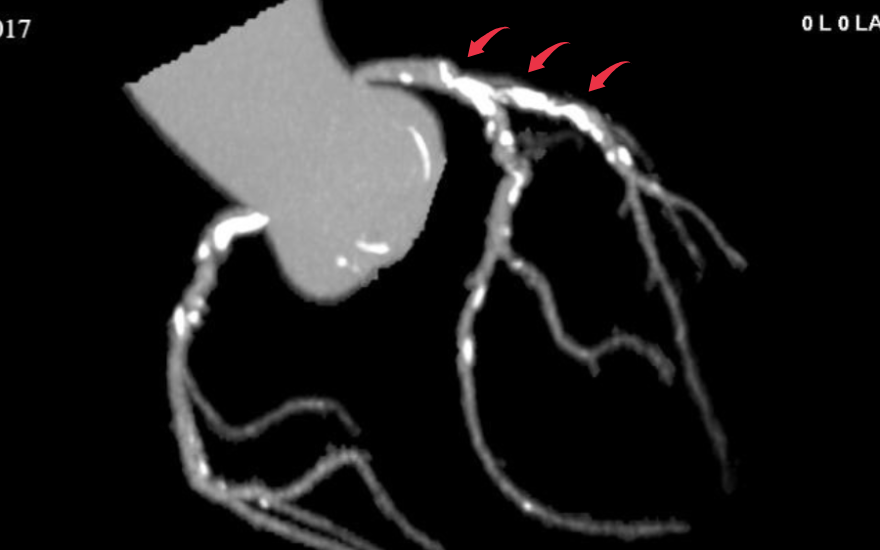

Là bác sĩ tiếp nhận thăm khám ban đầu cho người bệnh, ThS.BSNT Cao Mạnh Hưng - Khoa Tim mạch - Tim mạch can thiệp BVĐK Hồng Ngọc cho biết, ông N có những triệu chứng điển hình của bệnh mạch vành. Kết quả chụp CT mạch vành 2560 lát cắt đã cho thấy hai nhánh mạch vành của ông N bị hẹp nặng. Trong đó, động mạch liên thất trước hẹp khít do mảng xơ vữa, vôi hóa kéo dài 30 - 35mm, còn động mạch vành mũ hẹp khoảng 80%.

Mảng vôi hóa lan tỏa trên hình ảnh chụp CT 2560 lát cắt